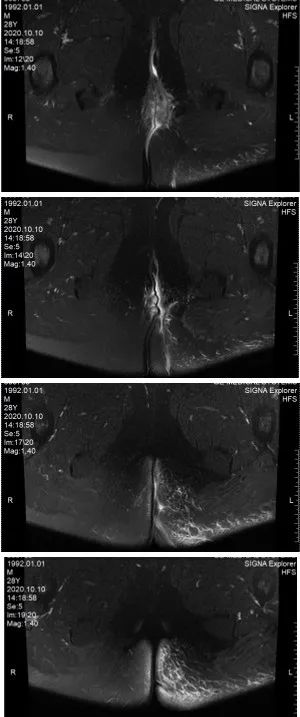

2020-09-28复查MRI

二次清创手术:如果患者生命体征继续恶化,在保证患者安全情况下,可行MRI检查以明确是否有残留坏死感染灶,必要时进行二次手术再次清创。常规换药时,对于小范围的坏死组织,应及时清创,平均需要3~4次清创。除了标准的术后血液检查和定期临床评估外,建议每6~8 h检测1次降钙素原、C-反应蛋白(C-reactive protein,CRP)和乳酸水平,因为这些实验室感染标志物有助于确定重复清创的时机。其中降钙素原与感染严重程度和器官功能障碍密切相关,也有助于指导抗菌药物的使用时间及疗效评估。